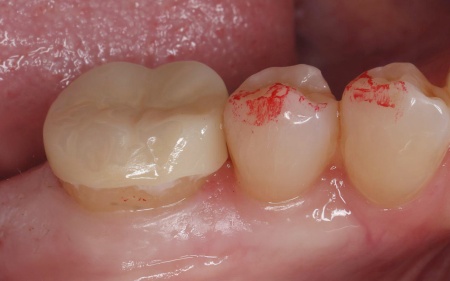

60代女性 欠けた奥歯を強度に優れたジルコニアのオンレーで修復した症例

拝見したところ、右下奥歯の一部が欠けている状態でした。

長期間にわたり噛む力が繰り返し加わったことで、奥歯に負担が蓄積して欠けてしまったと考えられます。

患者様は「周囲の歯になじむ自然な見た目で、長く安心して使える治療をしたい」と希望されていたため、通常の詰め物よりも広い範囲を覆う「オンレー」という修復方法を提案し、同意いただきました。

その後、オンレーがしっかりと合うように歯の形を整え、精密な型取りを行いました。

最後に、完成したオンレーを専用の接着剤で装着し、見た目や噛み合わせに問題がないことを確認して、治療を終了しました。